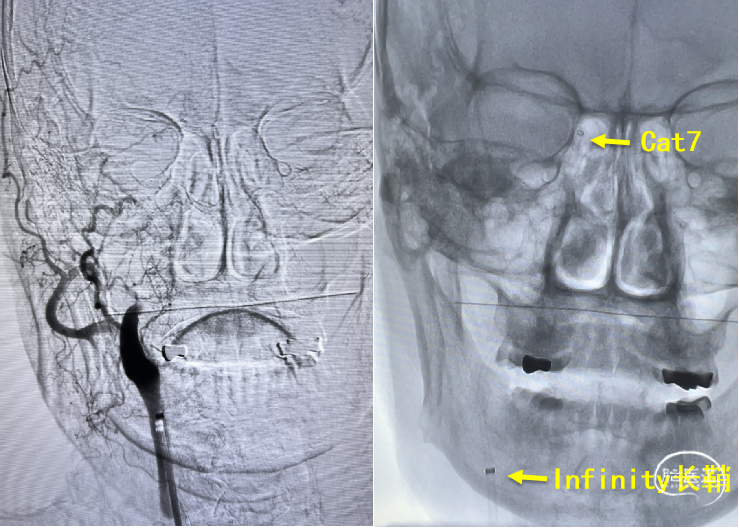

在Synchro2微导丝及微导管引导下,Catalyst7抽吸导管顺利到达颈内动脉末端。

Catalyst 7抽出大量负荷血栓,大脑中动脉上干仍未显影。

微导丝微导管超选至大脑中动脉上干,微导管造影确认在血管内真腔内,释放Solitaire 4×20mm。

Solitaire 4×20mm支架锚定Catalyst 7抽吸导管到达M1段,抽吸导管负压,拉出取栓支架,取栓过程中Catalyst 7维持稳定。

两次支架取栓取栓取出血栓,血管再通。